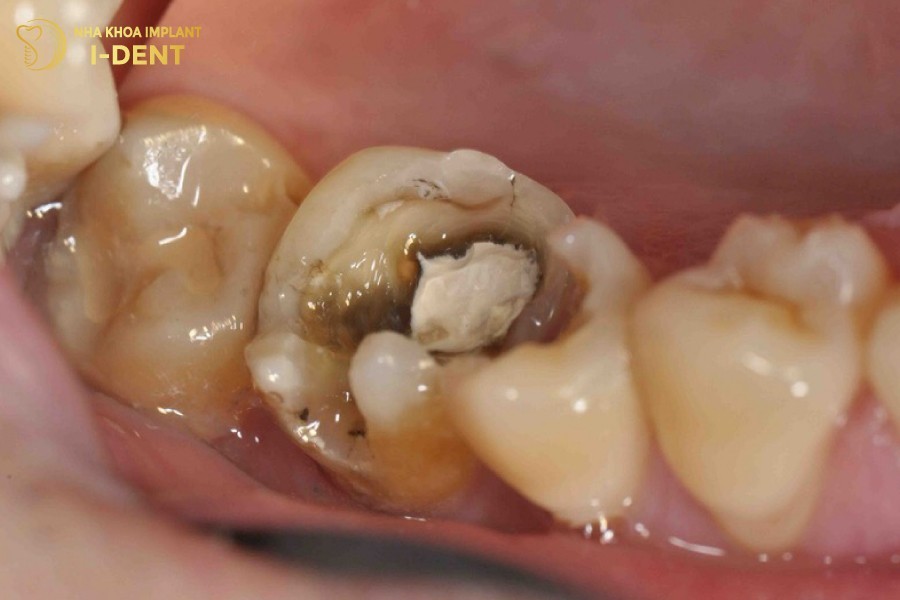

- Nhìn thấy lỗ sâu to: Do tổn thương ở men và ngà răng. Nếu lấy hết vụn bẩn thức ăn trong lỗ sâu, sẽ thấy đáy lỗ sâu rộng hơn miệng lỗ.

Lỗ sâu răng lớn trên bề mặt răng